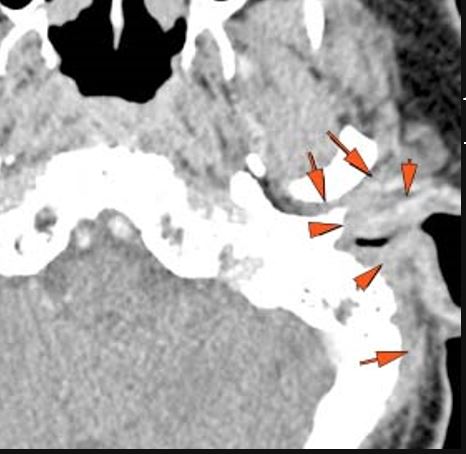

There is an erosive process, subperiosteal or otherwise spreading along the anterior-inferior aspect (extracranial aspect) of the petrous apex involving the bony Eustachian tube and/or carotid canal. [Yes/No]